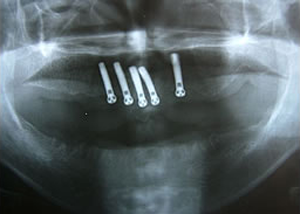

7.下の前歯部に4本

インプラント埋入

8.この部は薄い骨があっただけでインプラントの先端1/3を骨に埋入。あとはすべて骨を作ってあります。

上にのせた膜の中にチタンのフレームがわずかに映っています。